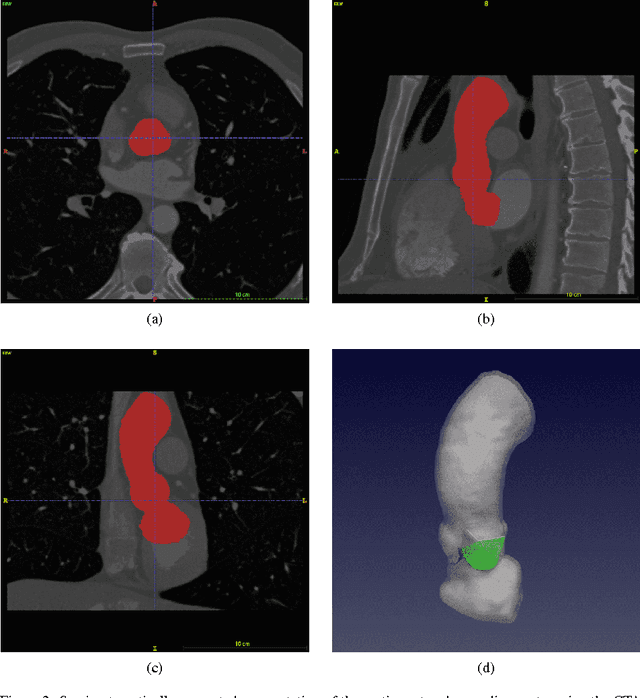

Abstract:Each year, approximately 300,000 heart valve repair or replacement procedures are performed worldwide, including approximately 70,000 aortic valve replacement surgeries in the United States alone. This paper describes progress in constructing anatomically and physiologically realistic immersed boundary (IB) models of the dynamics of the aortic root and ascending aorta. This work builds on earlier IB models of fluid-structure interaction (FSI) in the aortic root, which previously achieved realistic hemodynamics over multiple cardiac cycles, but which also were limited to simplified aortic geometries and idealized descriptions of the biomechanics of the aortic valve cusps. By contrast, the model described herein uses an anatomical geometry reconstructed from patient-specific computed tomography angiography (CTA) data, and employs a description of the elasticity of the aortic valve leaflets based on a fiber-reinforced constitutive model fit to experimental tensile test data. Numerical tests show that the model is able to resolve the leaflet biomechanics in diastole and early systole at practical grid spacings. The model is also used to examine differences in the mechanics and fluid dynamics yielded by fresh valve leaflets and glutaraldehyde-fixed leaflets similar to those used in bioprosthetic heart valves. Although there are large differences in the leaflet deformations during diastole, the differences in the open configurations of the valve models are relatively small, and nearly identical hemodynamics are obtained in all cases considered.